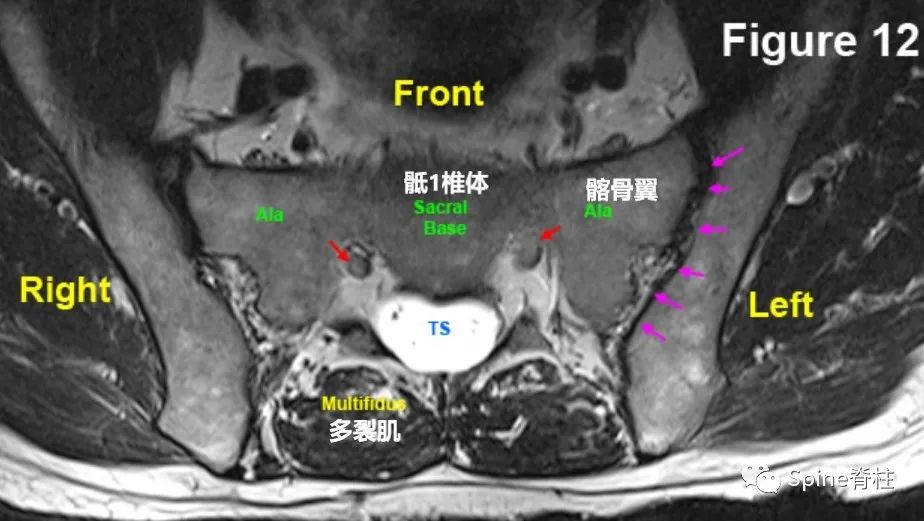

腰椎MRI的S1椎体水平。粉色箭头为骶髂关节,红箭头为S1走行根

MRI从S1椎体层面向上连续扫描,至4up的L5/S1椎间盘水平。在2up处可以看到右侧关节突(白色箭头),3up中S1走行根刚开始从硬膜囊中发芽形成独立囊鞘。4up可明确看到L5/S1椎间盘。其实,从2up开始就看到部分L5/S1椎间盘。